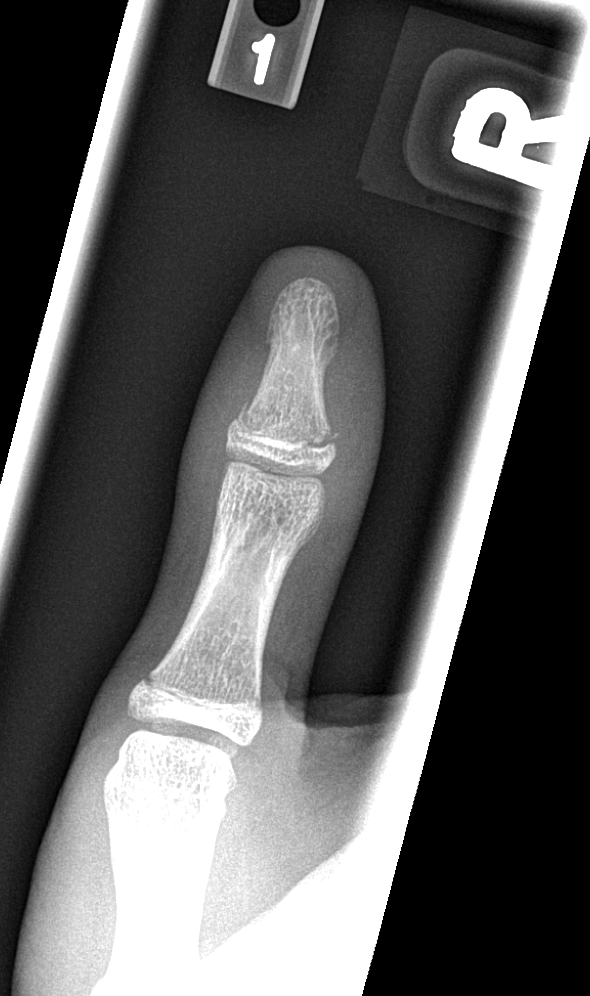

Info Images Findings Impression Reco/Acuity Case Images View Images / Launch Visage Case Notes History 2-month-old presents with decreased right arm movement, increased fussiness, and increased sleepiness for 2 days. Suspected non-accidental trauma. Exam Skeletal survey Prior Study none Dicom View Reference Material

Section 1 Submit Findings CB1550 Findings Skeletal Survey - Technique Check Skull AP/Lat Yes No Cervical and Thoracolumbar spine Yes No Chest X-Ray Yes No Ribs – Left/Right Oblique Yes No Abdominal X-Ray Yes No Pelvis with both hips Yes No Bilateral Humerus, Forearm, Hand Yes No Bilateral Femur, Tibia/fibula, feet Yes No Any additional lateral views of the extremities Yes No The exam is over or under penetrated. Yes No The exam may or may not be limited by overlying structures or soft tissues, body habitus, patient positioning, support devices, or motion. Yes No The area of concern is indicated by the patient, technologist, or care provider. Yes No The area of concern is included on the exam. Yes No Soft Tissues There is soft tissue swelling, indistinctness of fat/muscle planes, gas, or laceration in the area of clinical concern. Yes No There is an effusion, fat pad displacement, or fat fluid level. Yes No There is a radiodense or lucent foreign body. Yes No There are other densities, calcifications, post-surgical changes, or support devices in the soft tissues. Yes No Any support lines/tubes. Yes No Bone There is a break or interruption of the continuity of the cortical or cancellous bone. Yes No There is overriding of the trabeculae with apparent sclerosis. Yes No There is displacement of a fracture fragment. Yes No There is bowing of the bone in addition to the fracture at the apex of the bowed bone concerning for the greenstick. Yes No There is a spiral fracture of the leg concerning for toddler’s fracture. Yes No There is abnormal angulation or bulging of the cortical surface relative to the normal cortex which could be from a buckle or torus fracture. Yes No There is a displaced fragment which may be from avulsion by a tendon, ligament, or joint capsule or from a comminuted or other fracture. Yes No The stress trabeculae or other trabeculae of the cancellous bone are interrupted or otherwise abnormal. Yes No There is subperiosteal or endosteal reaction which could indicate a healing or subacute fracture or other abnormality. Yes No There is hard/soft callus formation. Yes No There is remodeling of the bone. Yes No There is a corner fracture or metaphyseal lesion that could be from nonaccidental trauma. Yes No There are multiple fractures of different ages. Yes No There are vertebral body/spinous process fractures. Yes No There are rib fractures. Location - posterior or lateral. Yes No There is scapular/sternal fracture. Yes No There are fractures of the digits. Yes No There are wormian bones. Yes No There are intrasutural bones. Yes No There is metaphyseal abnormality (lucencies, increased density, erosion) which may be from something other than injury such as stress, metabolic disease (e.g. rickets with loss or distortion of the zone of the provisional calcification), neoplasm (e.g. leukemia), heavy metals, inflammation, or infection. Yes No There are metaphyseal spurs. Yes No There are bony deformities involving multiple bones. Yes No The bones are gracile. Yes No There are non-healing fractures. Yes No There is/are focal or multifocal lytic/lucent, blastic/sclerotic or mixed density lesion(s) or other abnormality. Yes No Overall bone density is increased or decreased with or without thinning or thickening of the cortical or cancellous bone. Yes No Growth plates, ossification centers, apophyses The growth plate(s) is/are abnormal. Yes No There is widening of the physis from a fracture with or without displacement of the epiphysis (Salter-Harris I). Yes No There is a fracture through the physis which then extends into the metaphysis with or without angulation or displacement (S-H II). Yes No There is a fracture through the physis which then extends into the epiphysis and is intra-articular, with or without angulation or displacement (S-H III). Yes No There is a fracture through the metaphysis, physis, and epiphysis which extends into the joint space with or without angulation or displacement (S-H IV). Yes No There is narrowing of the physis from a compression fracture (S-H V). Yes No The apophysis, epicondyle, secondary ossification center, or accessory ossicle is displaced or otherwise abnormal. Yes No The ossification centers are underdeveloped. Yes No Joints and alignment There is an effusion, fat pad displacement, or fat fluid level. Yes No The epiphysis or subchondral bone is fractured, interrupted, flattened, compressed, impacted, displaced, or otherwise abnormal. Yes No There is an intra-articular loose body or chondrocalcinosis. Yes No The joint is widened, narrowed, dislocated, malaligned, or incongruent. Yes No There is pseudoarthrosis. Yes No Other findings There are developmental changes or other anatomic variants or other existing conditions that may or may not be contributing to symptoms which can or should be further evaluated non-emergently or are otherwise incidental. Yes No The remainder of the exam is abnormal for age. Yes No The lungs show focal airspace opacity. Yes No There is pneumothorax. Yes No There is organomegaly. Yes No There is intra-abdominal calcification. Yes No There is displacement of the bowel loops. Yes No There is free intraperitoneal air. Yes No The bowel loops are dilated/obstructed. Yes No There is paraspinal soft tissue abnormality. Yes No